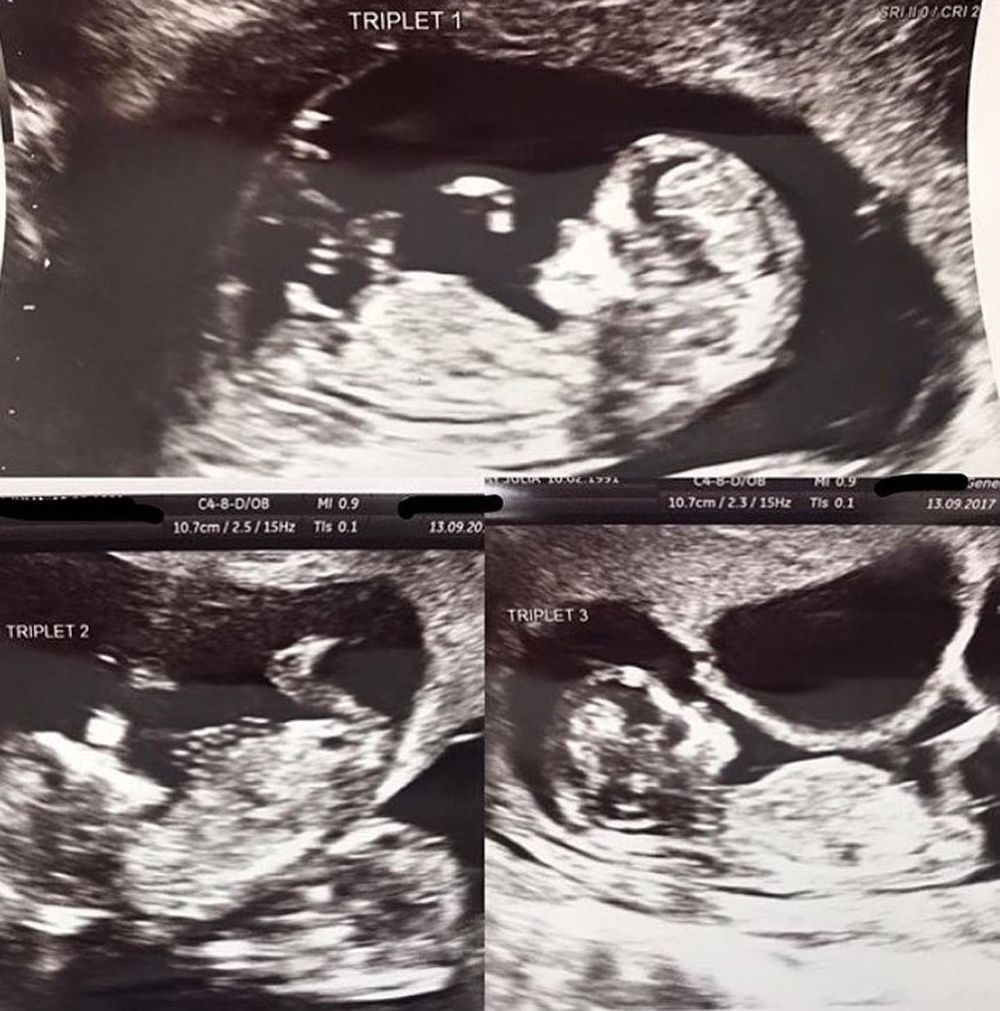

More amazing news came at her six-week scan, when midwives announced that she was having triplets.

“We'd wanted a baby for so long, and now we were having three. Going from a two to a five was scary, but so exciting," said Craig. “Amy was so strong, and from the very moment I knew they were coming, I loved my three babies more than anything in the world."